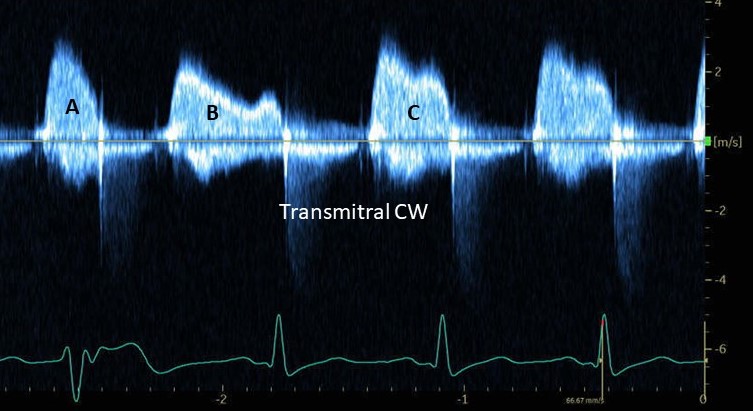

Wonderful day of learning at North Florida Cardiovascular symposium alongside my fellow IM residents and CV fellows at Orange Park! Congrats on winning the poster competition Sadhana Jonna and for an amazing case presentation haris ahmed

DIGIT-HF trial has started a snowball effect in heart failure research! Are we in front of the fifth pillar in HFrEF? 🤔 .. Watch my interview with John Mandrola John Mandrola, MD from Louisville, Kentucky, USA and see his 5 learnt lessons from this trial. #ESCCongress European Society of Cardiology